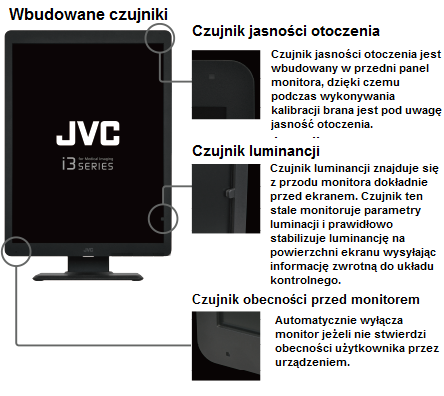

Samodzielna kalibracja

Zintegrowany czujnik przedni w monitorach serii i3 pozwala na samodzielne, zgodnie z ustawionym harmonogramem, wykonanie przez monitor okresowej kalibracji do standardu DICOM.

Czujnik przedni